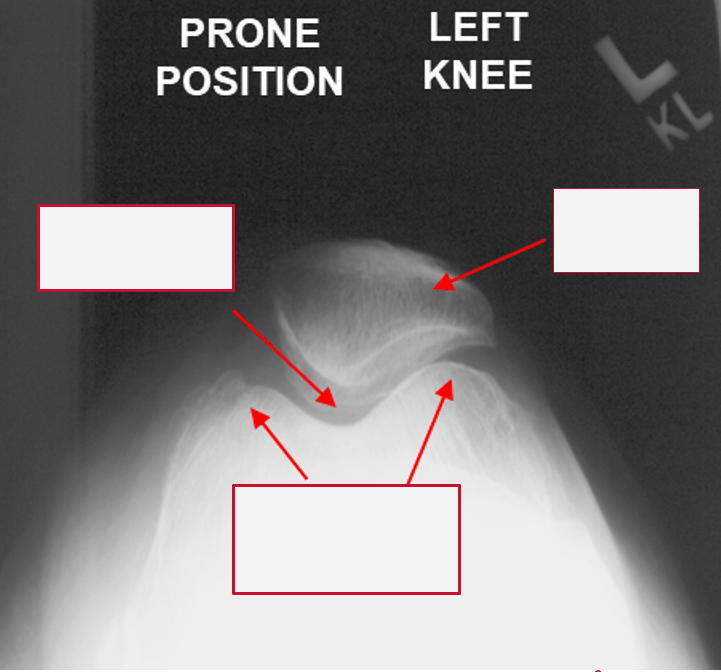

Label the areas on X-ray

1. Patella Articulation

2. Patella

3. Femoral Condyles